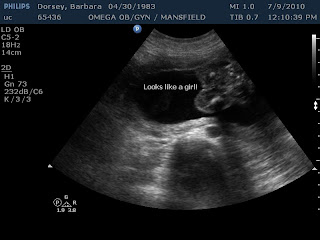

At 20 weeks we saw our sweet baby and found out it was a girl!! We were absolutely shocked because we were so sure it was a boy. Well actually I felt from the beginning it was a girl, but I think Matt talked me into thinking it was a boy... wow what a great surprise.. not that it mattered! But, I get to buy lots of bows and pink now!